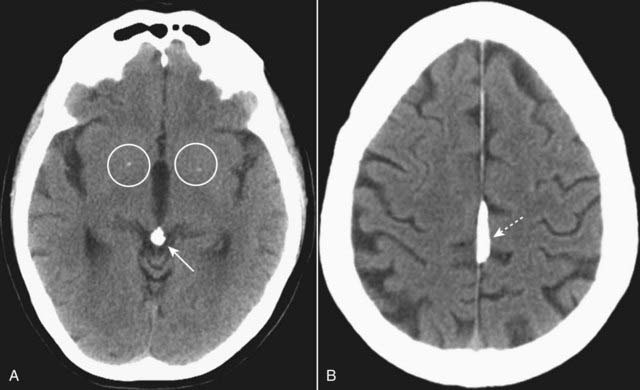

imageOn an unenhanced CT scan of the brain, anything that appears “white” will generally either be bone (calcium) density or blood in the absence of a metallic foreign body (Table 25-2).

image Calcifications that may be seen on CT of the brain which are nonpathologic:

Pineal gland (Fig. 25-2A)

Basal ganglia (see Fig. 25-2A)

Choroid plexus (see Fig. 25-1F)

Falx and tentorium (Fig. 25-2B)

image

Figure 25-2 Physiologic calcifications.

A, There are small, punctate calcifications in the basal ganglia (white circles) and calcification of the pineal gland (solid white arrow). B, Calcification of the falx cerebri is present (dotted white arrow). Anything that appears white on a noncontrast enhanced CT of the brain is either calcium or blood. Physiologic calcifications tend to increase in incidence with advancing age.